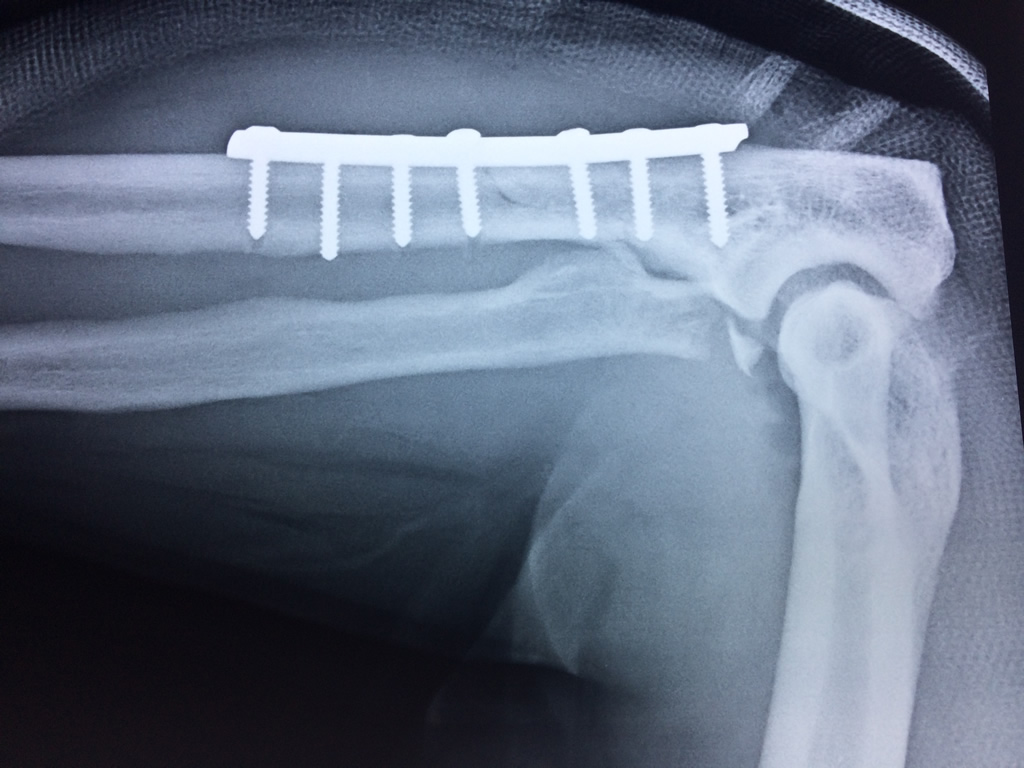

Cirugías de Húmero - Codo

En anatomía humana, la articulación del codo es la que une el brazo con el antebrazo, conectando la parte distal del hueso húmero con los extremos proximales de los huesos cúbito y radio.

La articulación principal que constituye el codo se denomina humero radio-cubital y puede dividirse en dos partes bien diferenciadas, la articulación humero-radial y la humero-cubital.